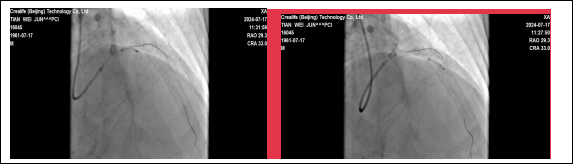

贵州航天医院心血管内科 应用国产冲击波球囊系统 完成严重钙化病变手术 近日,我院心血管内科团队成功为一名急性心肌梗死合并冠脉重度钙化患者实施了“冲击波球囊术”。手术取得了显著效果,术后患者症状明显改善。 63岁田先生,因胸痛2小时就诊我院心血管内科,经冠脉造影检查,提示:冠脉前降支的近中段弥漫性狭窄约80%-95%,局部明显“钙化影”。血管内的钙化病变就是导致患者胸痛的根本原因。 术前:前降支冠脉弥重度狭窄,伴钙化。 术中:冲击波球囊释放脉充、扩张。 心血管内科姜黔锋团队经过认真研究病情、冠脉造影图像,考虑到老年患者冠状动脉钙化重、血管迂曲的情况,进行常规冠脉旋磨风险大,单纯球囊扩张,难以取得满意的效果,在衡量多种手术方案,取得患者及家人同意后,决定采用血管内冲击波球囊治疗技术进行治疗,重点解决因冠脉重度环形钙化,直接支架植入贴壁不良,支架内在狭窄,急性血栓形成影响远期预后等的问题。 术后:支架植入后,血管畅通,效果良好。 针对此情况,由沈万贵主任担任术者,通过双导丝、预扩张球囊等进行预处理后,精准将冲击波球囊送至病变处,经释放脉冲后,OCT(经光学相干断层扫描的冠状动脉血管内影像)证实钙化病变已经完全打开,后扩张球囊充分扩张钙化病变处,很快达到了理想的手术条件,顺利完成支架植入。术后患者血管狭窄消失,血流通畅,胸闷、胸痛症状明显缓解,达到了预期的治疗效果。 我院心血管内科首次应用国产冠脉冲击波治疗系统完成手术,凭借丰富的手术经验和技巧,助力患者重获新生,标志着我院心血管内科冠脉血管钙化病变介入治疗技术再上新台阶,将为更多复杂、严重冠脉钙化患者带来“心”希望。未来,心血管内科团队将继续开拓进取,紧跟学科前沿,积极应对人口老龄化、心血管疾病复杂化,努力为患者提供规范、高质量的医疗诊疗技术服务。 延伸阅读 01 什么是冲击波球囊技术? 冲击波球囊技术,或称血管内碎石术,源自泌尿系统结石治疗的碎石原理,经过结合球囊成形技术的创新发展,成为一项新的治疗技术。 采用声压力波有针对性地作用于冠状动脉内膜及中膜下的钙化病灶,在不影响血管内膜完整性的情况下,有效地震松或震裂钙化病灶,恢复血管顺应性,为后续冠脉支架的植入提供更理想的管腔。 02 冲击波球囊技术的优势? 1.能够在不损伤血管壁的情况下,有效碎裂钙化物质,提高血管顺应性,为后续的支架植入手术创造更好的条件; 2.术中血管夹层、穿孔、远端栓塞、慢血流、无复流等并发症风险显著降低; 3.操作简便、安全性高、疗效显著; 4.是目前唯一能够有效处理浅层和深层钙化的技术。 贵州航天医院心血管内科简介 贵州航天医院心血管内科是遵义市市级重点专科,遵义市远程心电示范中心,遵义市高血压慢病管理示范中心。近年来成功获得胸痛中心标准版、房颤中心标准版,儿童先天性心脏病定点救治单位授牌,编制床位60张,科室配置了29台24小时动态心电图、110台24小时动态血压、心脏除颤仪、监护仪、输液泵、微量注射液,同步12导联、18导联心电图机、临时心脏起搏器、床旁血糖仪、主动脉内球囊反搏、食道超声、血管内超声诊断仪及DSA心血管诊疗等。 开展了急诊冠脉介入诊疗,冠脉复杂病变介入术、冠状动脉斑块旋磨术、心脏再同步治疗起搏器植入术、心脏再同步治疗除颤器植入术、射频消融术【心房颤动(导管消融、冷冻消融)、心房扑动、房性心动过速、室性心动过速、室性早搏】、结构性心脏病介入治疗【房间隔缺损(卵圆孔未闭)封堵术、室间隔缺损封堵术、动脉导管未闭封堵术、冠状动脉瘘封堵术、左心耳封堵术等】、临时起搏器植入术、常规永久起搏器植入术(双腔、单腔)、下肢动静脉造影术、下腔静脉滤器植入及取出术、自主肾上腺静脉采血、颈动脉支架植入术、外周动脉支架植入术、肾动脉支架植入术等,积极开展冠脉内超声检查、FFR、OCT、心脏射频三维手术,同时开展了房颤一站式治疗(房颤射频消融术+左心耳封堵术)、主动脉瓣介入术等,在外院专家指导下完成腹主动脉支架植入术。 心血管内科门诊时间及地点 心内科门诊地点及就诊时间 门诊一楼012/013诊室 周一至周五(08:00-17:00) 周六、周日及节假日(08:00-16:00) 心内科咨询电话 一、病房护士站:0851-28611793(外科综合楼9楼) 二、医生办公室:0851-27677832 三、心内科门诊:0851-28614631 四、心内科总值班电话:17785233019 科室专家 注:部分图片来源于网络,如有侵权,请联系删除。 精彩推荐 供 稿:曹昌强(心血管内科) 编 辑:唐语蔚 一 审:沈万贵(心血管内科) 二 审:陈 伟 三 审:蒙昌耀